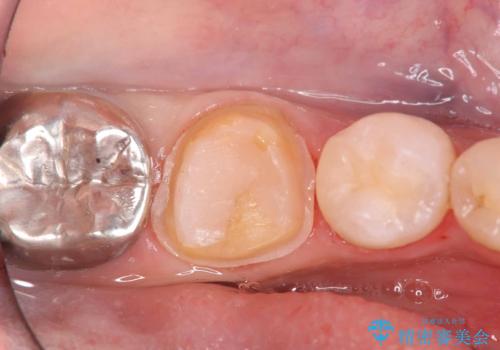

- 銀歯の下の虫歯です。お写真で分かるように広範囲で深い虫歯でした。

1歯はオールセラミッククラウンもう1歯はセラミックインレーで治療を行いました。

かなり虫歯が大きく深かったですが、神経は取らずに残す事が出来ました。